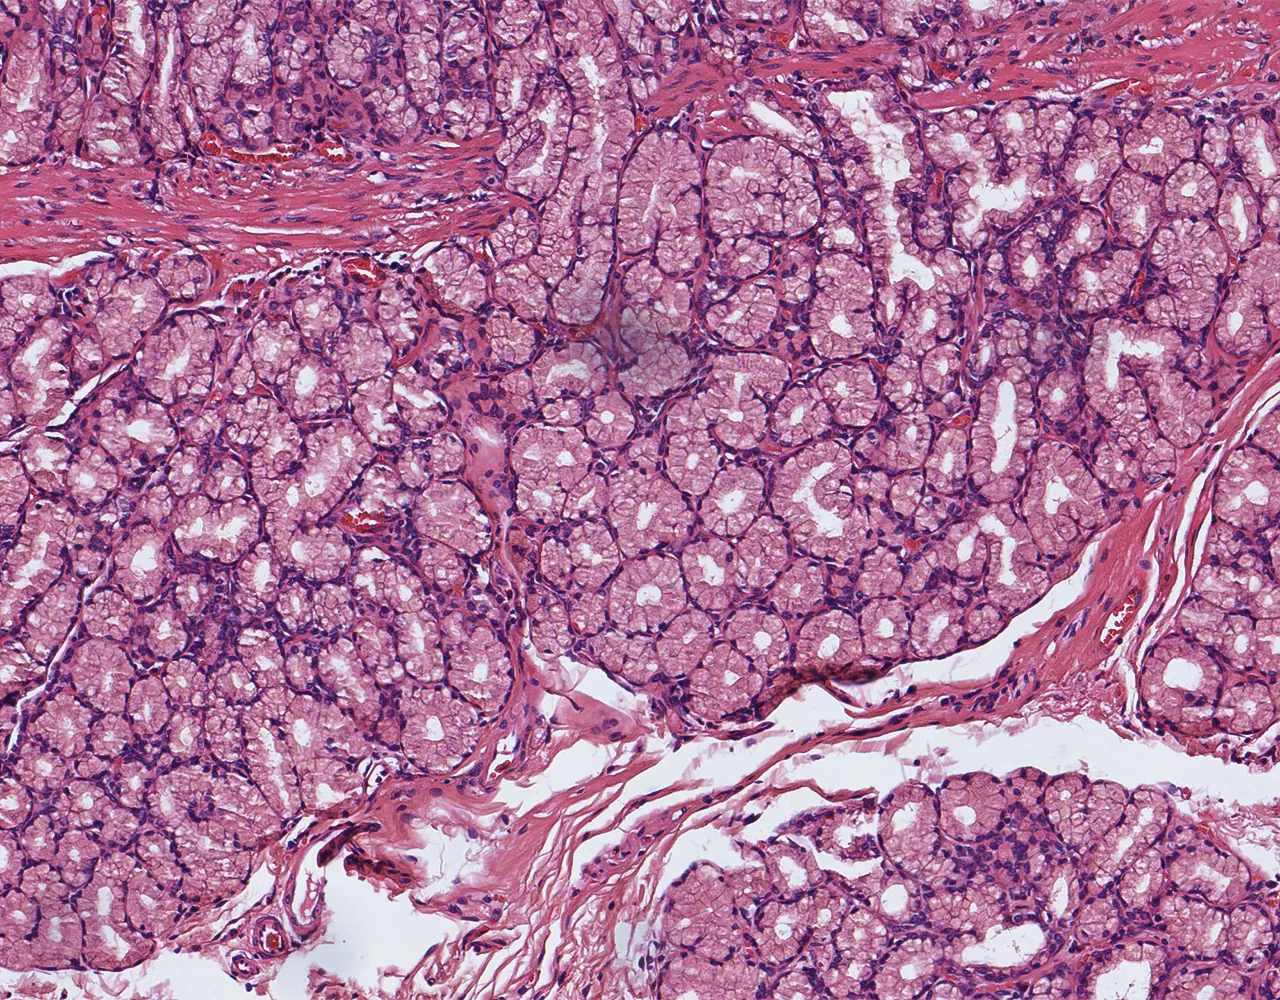

- The absorptive surface area of the small intestine is amplified by three structural levels: plicae circulares, villi, and apical microvilli forming the brush border.

- Microscopically, the wall is composed of 4 layers from the inside outward: mucosa, submucosa, muscularis propria, and serosa.